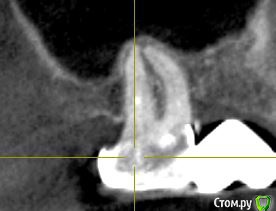

ТСВ Опубликовано 29 июня, 2015 Поделиться Опубликовано 29 июня, 2015 Подскажите пожалуйста!17 зуб, на нем мост. Сделал КТ, там такая картина, прикрепляю несколько срезов.Если это киста, то только удаление вместе с зубом? Ссылка на комментарий

red_butler Опубликовано 29 июня, 2015 Поделиться Опубликовано 29 июня, 2015 Кисты нет, а вот повторное лечение корневых каналов требуется 2 Ссылка на комментарий

Alejandro Опубликовано 30 июня, 2015 Поделиться Опубликовано 30 июня, 2015 Вы имеете в виду очаг просветления в области середины дистального щёчного корня? Ссылка на комментарий